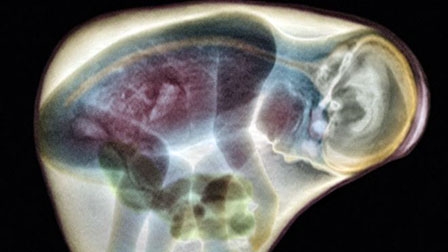

Chụp MRI giúp tầm soát kịp thời sức khỏe não bộ của thai nhi